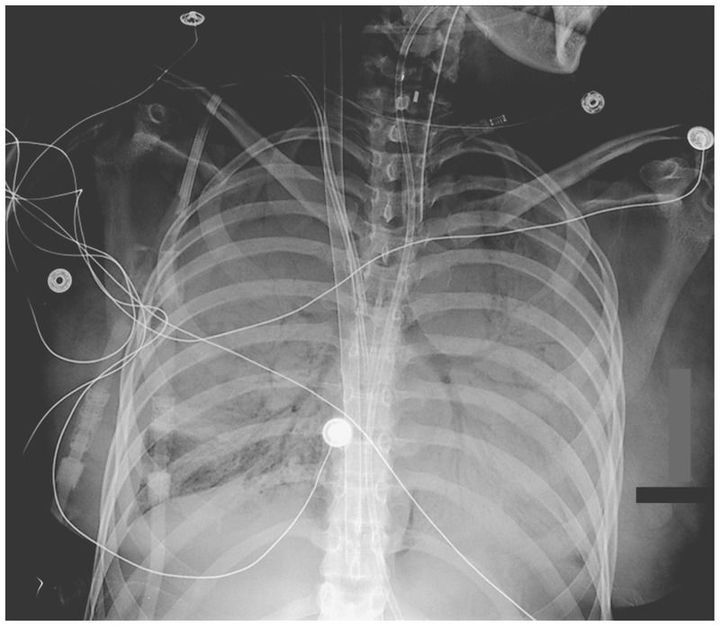

A 26-year-old woman with end-stage renal disease secondary to lupus nephritis presented with a 3-day history of fever, cough, and shortness of breath, symptoms that are consistent with pneumonia. The acute respiratory distress syndrome (ARDS) developed, and the patient ultimately required extracorporeal membrane oxygenation (ECMO) after the failure of mechanical ventilation. A dual lumen ECMO catheter was placed in the right internal jugular vein to drain blood from the superior and inferior vena cavae and return it to the right atrium. Portable anterior–posterior chest radiography showed dense airspace disease with bilateral hemithorax opacification and air bronchograms, a radiologic sign in which the air-filled bronchi are visible as a consequence of the opacification of the surrounding alveoli. Shortly thereafter, cultures from bronchoalveolar lavage revealed Moraxella catarrhalis and Haemophilus influenzae. The patient was treated with appropriate antibiotics, renal-replacement therapy, and supportive care. She was successfully removed from the ECMO circuit after 9 days and weaned from the mechanical ventilator 4 days later. She was discharged to an inpatient rehabilitation facility and continued to do well at the 6-month follow-up.